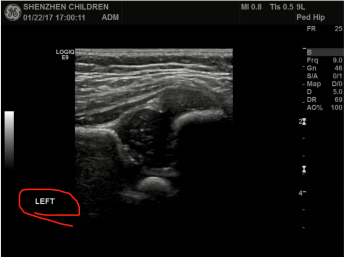

人体髋关节。对每一个人的髋关节有左右两个图像。

目前我们标记的数据,都是从视频中找出左侧骨头最水平的一张,抽出来标记。